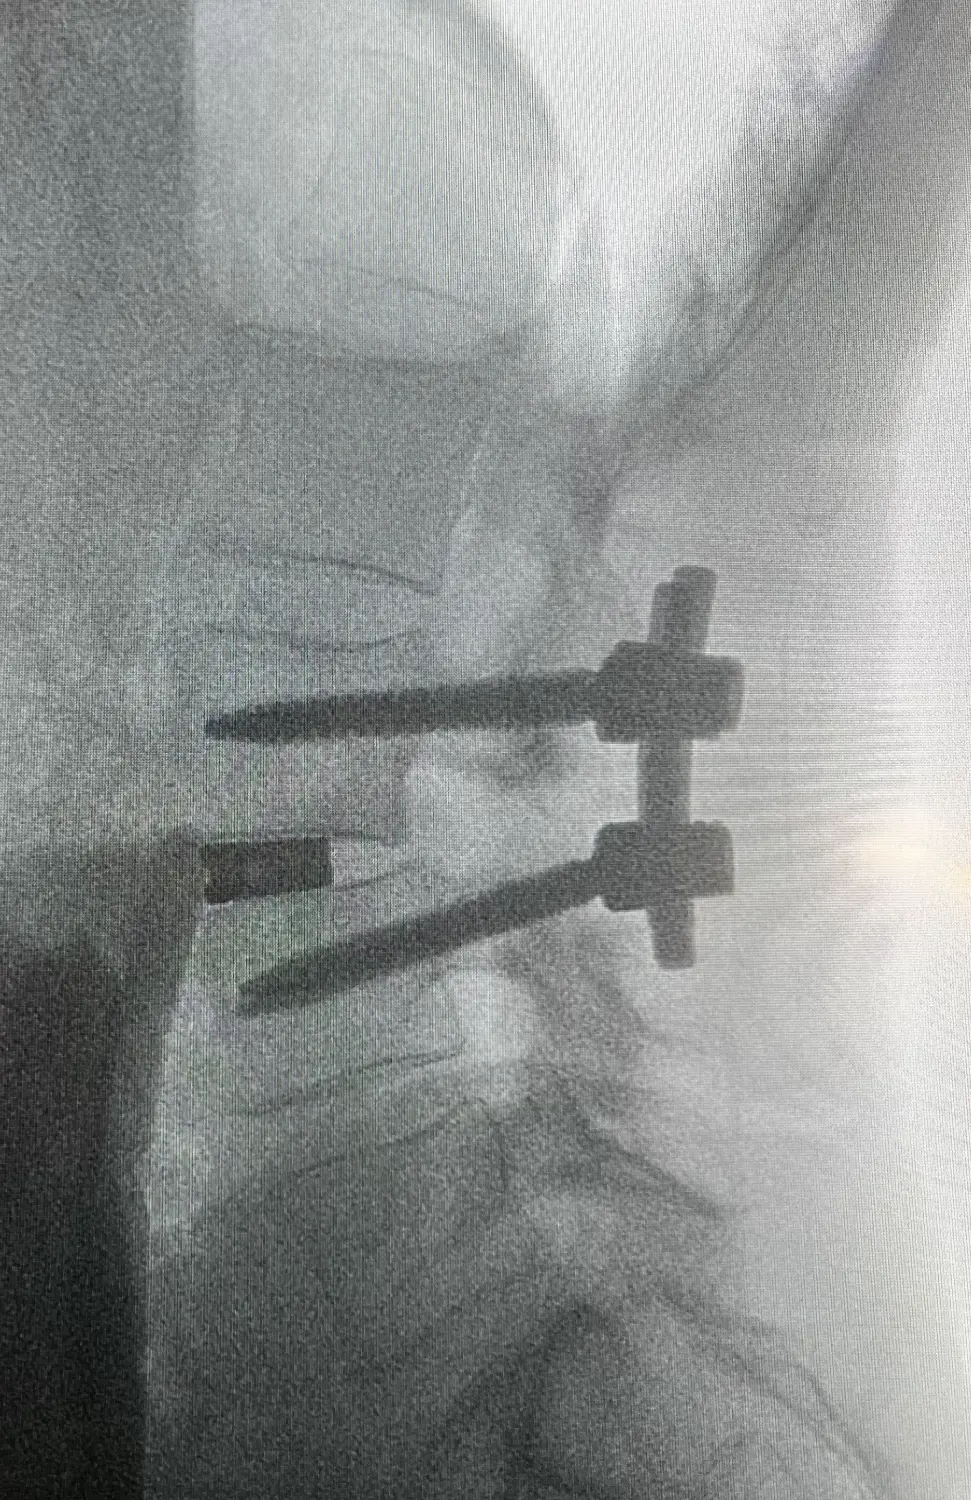

Nur wenn konservative Maßnahmen keine ausreichende Linderung bieten oder die Osteochondrose zu neurologischen Symptomen (Kraftminderung, Nervenschmerzen oder sensible Defizite) führt, sollte ein chirurgischer Eingriff erwogen werden. Die Art der Operation muss in jedem Fall individuell mit dem Patienten besprochen und geplant werden. Durch schonende Verfahren und innovative Implantatsysteme kann eine postoperative Bewegungseinschränkung auf ein Minimum beschränkt werden. In der Regel wird die zerstörte Bandscheibe durch ein Implantat aus Titan ersetzt und die ursprüngliche Form der Wirbelsäule rekonstruiert. Titanschrauben garantieren die höchstmögliche Stabilität des operierten Segments. Sollte eine ausgeprägte Osteoporose (Knochenschwund) vorliegen, können die Schrauben zusätzlich mit Knochenzement verstärkt werden.